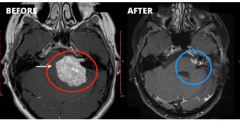

在手术过程中,头骨的一部分被移到耳朵后面,以接近肿瘤和神...